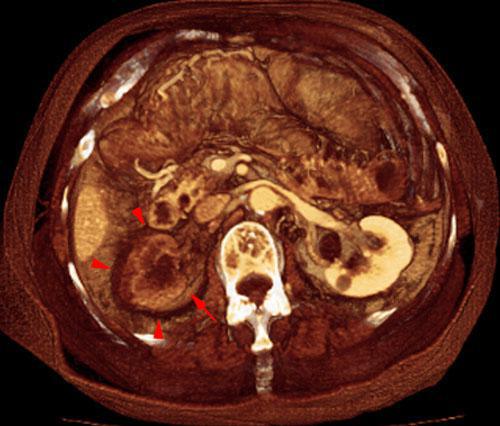

Infartos renales múltiples